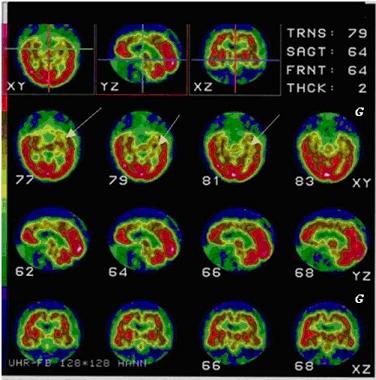

Scintigrafia cerebrală –SPECT, tehnica imagistică funcţională, este deosebit de utilă pentru diagnosticul de BA deoarece modificări semnificative ale perfuziei cerebrale apar cu predilecţie în regiunile asociative posterioare ale cortexului, mai rar în cortexul prefrontal. Scintigrafia se efectuează cu radiofarmaceutice care difuzează prin bariera hematoencefalică integră (Tc99m-HMPAO), fiind o tehnică simplă şi puţin iradiantă. În faza precoce a bolii, anomaliile de perfuzie depistate sunt variabile, frecvent asimetrice, uneori unilaterale, reflectând eterogenitatea lezională. Hipoperfuzia la nivel temporal posterior se asociază cu o valoare predictivă pozitivă semnificativă, pe când obţinerea unei imagini normale a perfuziei cerebrale temporo-posterioare are o valoare predictivă negativă înaltă. Ulterior, în stadii avansate, apar deficite majore de perfuzie la nivel parietal şi frontal.

În contextul apariţiei permanente a multiple noutăţi terapeutice, scintigrafia cerebrală de perfuzie - SPECT - poate juca un rol important nu numai în diagnostic, ci şi în monitorizarea eficienţei terapeutice.